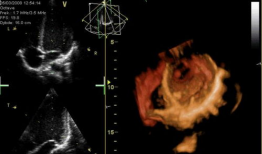

心脏跳动的视频,揭秘心脏跳动的奥秘

你知道吗?最近在网上流传着一个特别神奇的视频,它记录了心脏跳动的瞬间。这可不是普通的视频,它让我们仿佛能感受到心跳的力量,那种感...